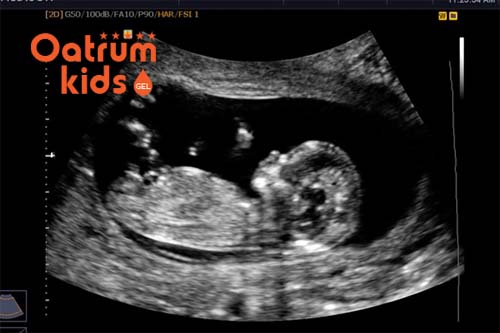

Đặc biệt thai nhi tuần thứ 12 sẽ có nhịp tim cao hơn cả người trưởng thành, các mẹ cũng có thể nghe rất rõ nhịp đập này của bé khi siêu âm. Hầu hết cơ quan quan trọng của thai nhi đều đã hình thành và đang bắt đầu thực hiện chức năng của mình.

Kích thước thai nhi 12 tuần tuổi có chiều dài khoảng 5,3cm được tính từ đầu đến mông, cân nặng của bé khoảng 28gr, có gần như đầy đủ bộ phận và tiếp tục phát triển trong thời gian tới. Do đó mẹ cần chăm sóc bản thân cho tốt để con phát triển.

Ở giai đoạn này, bộ phận sinh dục của bé cũng đã được hình thành rõ, vì thế nếu siêu âm tốt có thể nhìn được là bé trai hay gái. Tuy nhiên độ chính xác ở thời điểm này cũng chỉ dao động tầm hơn 80% chứ không thể chính xác được 100% về giới tính của bé.

Thai nhi tuần thứ 12 đã có thể chẩn đoán được giới tính.